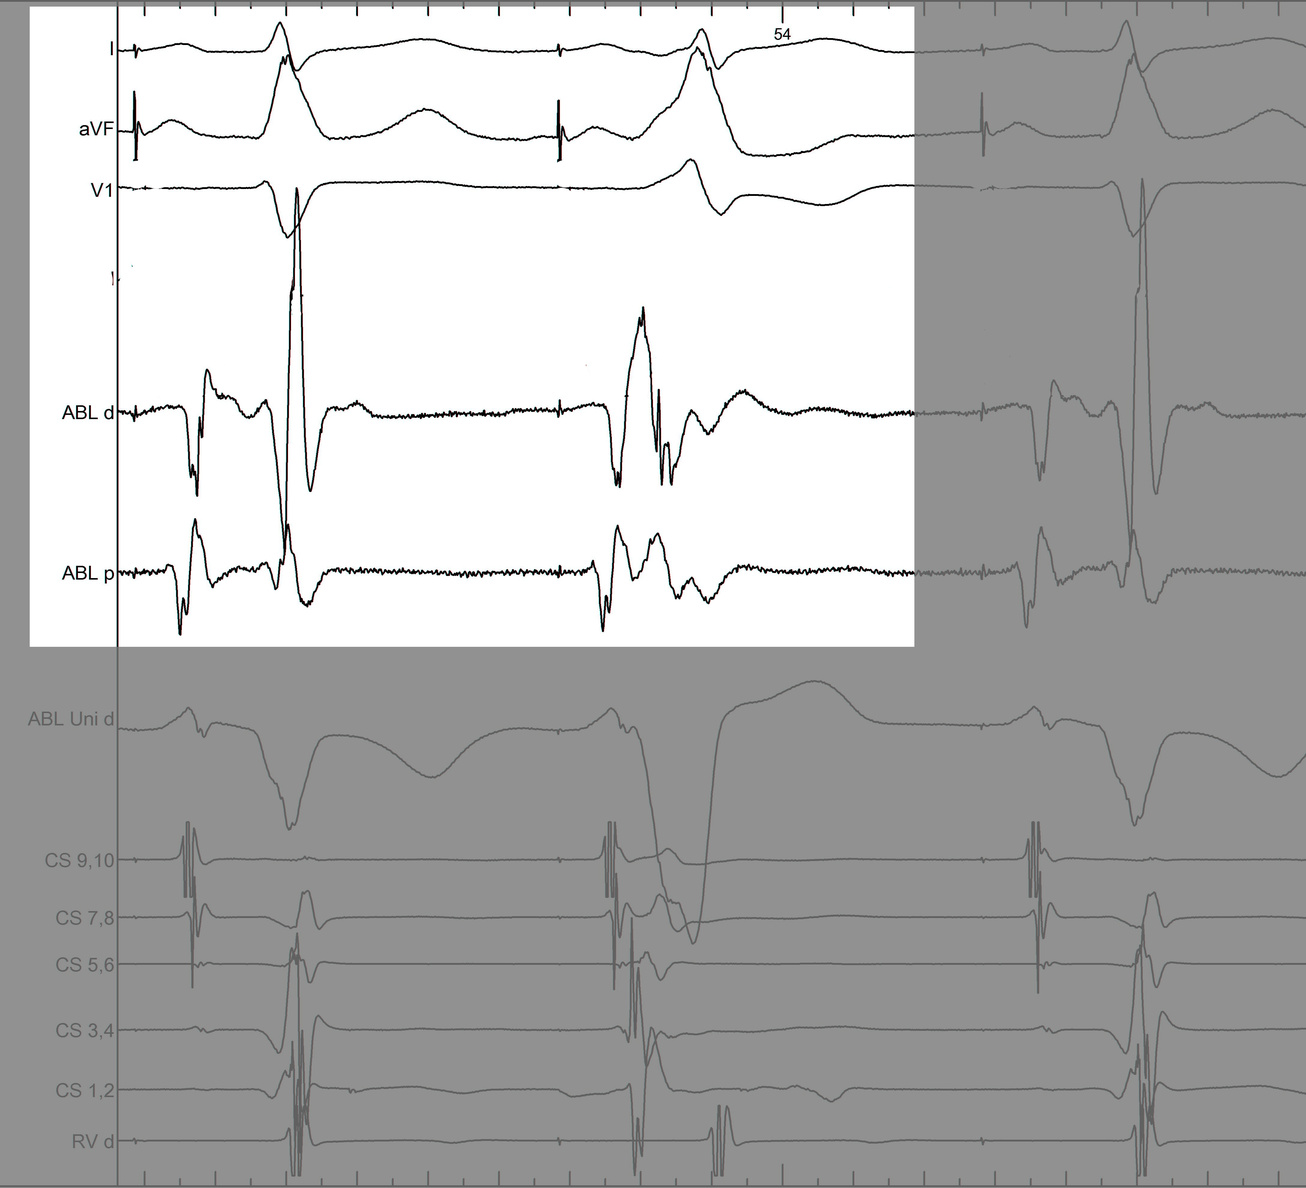

#4 Key to mapping is to identify signal components

mask1.jpg

mask2.jpg

mask3.jpg

mask4.jpg

pseudo_disappearance.jpg